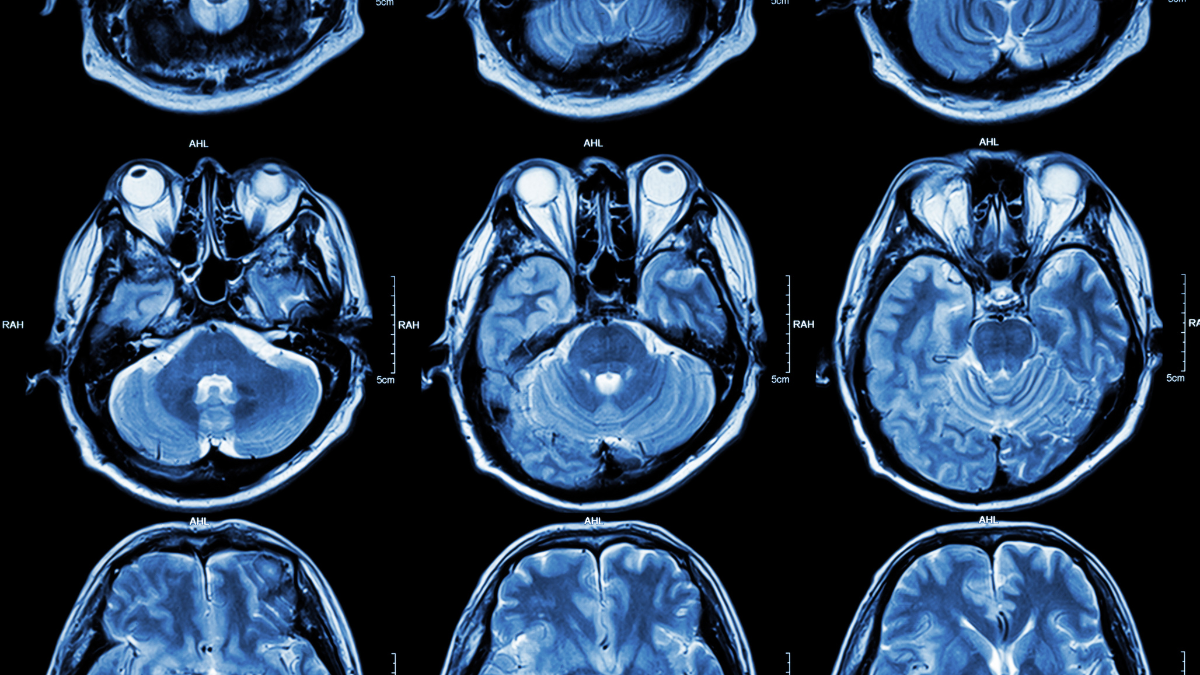

For decades, Alzheimer’s research has focused on amyloid plaques – abnormal clusters of protein that accumulate in the brain and disrupt neuronal function. This new research suggests that lithium, a naturally occurring metal vital for brain health, is actively captured by these amyloid plaques. This isn’t a passive process; the study indicates that the capture of lithium actually accelerates neurodegeneration, creating a dangerous feedback loop. Essentially, the brain loses lithium, which allows more amyloid to build up, which then traps even more lithium.

“This discovery confirmed that the amyloid captures lithium of the surrounding tissues and the sequestration,” explains the Nature article. The research team, which also included scientists from Rush University, compared metal concentrations in post-mortem brain tissue, finding lithium to be the only significantly reduced metal in the brains of Alzheimer’s patients, even at early stages of cognitive impairment.